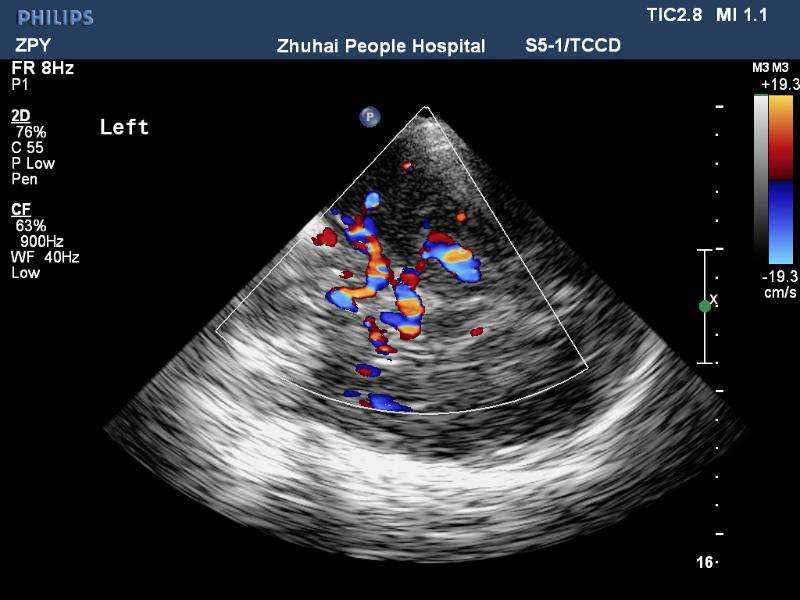

經顱彩色編碼雙功能超聲(transcranial color-coded duplex sonography

TCCD)是一種非侵入性發現顱內動脈異常血流動力學狀態的可靠方式。TCCD成像原理是在TCD基礎上增加了二維灰階實時顯像以及彩色編碼雙功能超聲成像,在二維顯示顱內解剖結構的同時,同時對運動紅細胞產生的多普勒頻移進行彩色編碼。應用TCCD檢測時可以通過在感興趣區內多點取樣,得出取樣容積內多普勒頻移曲線,通過雙側對比、左右對比以及前后對比,綜合評價缺血性腦血管病受檢者Willis環的血流動力學變化。

TCCD成像圖片

依據多普勒頻移值編碼成像即f-TCCD:依賴運動紅細胞所產生的多普勒頻移值進行計算機編碼,可以顯示血流方向和測算血流速度,需要校正多普勒取樣角度,角度及篩查深度依賴性較大,較易產生運動偽像。(2)依據運動紅細胞所產生的總能量進行編碼成像即p-TCCD:只與運動紅細胞所產生的總能量有關,無需校正多普勒取樣角度,對于受取樣角度影響較大血管病變,諸如大腦后動脈(PCA),大腦中動脈(MCA)M2段,大腦前動脈(ACA)A1段有一定的幫助作用,信噪比更高,不易產生混疊效應。p-TCCD相對f-TCCD而言,缺點是不能顯示血流方向,對顯示狹窄處高速血流敏感性較低。